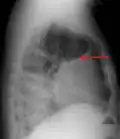

A pleural effusion as seen on lateral upright chest x-ray -

Pleural effusion as seen behind the heart.[20]

A pleural effusion appears as an area of whiteness on a standard posteroanterior chest X-ray.[15] Normally, the space between the visceral pleura and the parietal pleura cannot be seen. A pleural effusion infiltrates the space between these layers. Because the pleural effusion has a density similar to water, it can be seen on radiographs. Since the effusion has greater density than the rest of the lung, it gravitates towards the lower portions of the pleural cavity. The pleural effusion behaves according to basic fluid dynamics, conforming to the shape of pleural space, which is determined by the lung and chest wall. If the pleural space contains both air and fluid, then an air-fluid level that is horizontal will be present, instead of conforming to the lung space.[16] Chest radiographs in the lateral decubitus position (with the patient lying on the side of the pleural effusion) are more sensitive and can detect as little as 50 mL of fluid. Between 250 and 600mL of fluid must be present before upright chest X-rays can detect a pleural effusion (e.g., blunted costophrenic angles).[17]